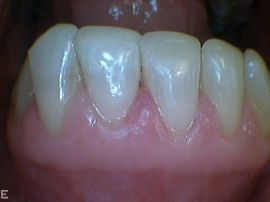

- Metallfreie Keramikkronen und Verblendschalen aus Porzellan (laborgefertigt), vor allem für ästhetisch wichtige Zähne

- Ästhetische Verbesserung von verfärbten oder leicht schiefen Zähnen mit kostengünstigen Komposit-Überzügen